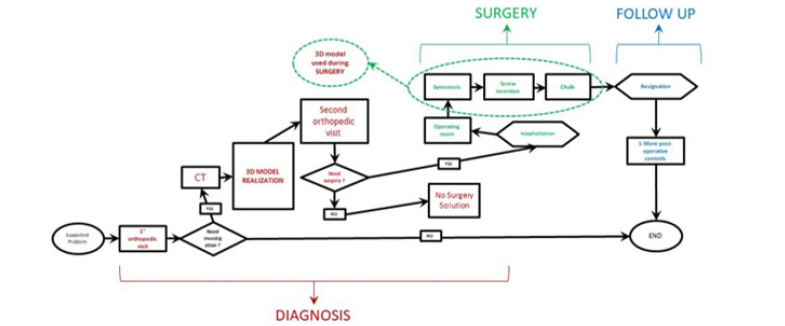

Cost Analysis

The realization of the three-dimensional model involves a series of costs:

1. Purchase of the 3D printer

2. Labor cost

3. Material cost

4. Software

The costs relative to this specific printed model are summarized in (Table 5). The cost of the printer is about 220 € and its useful life is approximately of 2000 working hours. The labor time required for the conversion and the cleaning of the model is 4 hours average and the estimated cost of the specialized operator is 20 €/h. For the printing of the model it is necessary an average of 0,250 kg of material. The actual printing time to get the 3D model is 22 hours. The software used in the proposed procedure are all open source and they don’t imply added costs.

Innovative Procedure Profits

Using a three-dimensional reproduction with the new workflow allows to save money in a cost analysis. In the diagnosis phase the number of orthopedic visits fell from 3 to 2 for each patient decrease by 33.4% or saving 18 €/patient. Moreover, the 3D model allows to bypass the first radiological step so the number of radiological visits per patient is halved avoiding the expense of 21 €/ patient. The traditional surgical intervention was about 60 minutes average. Using the prototype, the time frame should be reduced by 15 minutes or 25% less This reduction in use of the operating room costs 206.75 €/ patient less. Finally, studying the case on the 3D prototype decrease the recurrence rate of 15% compared to the traditional case (only CT used). Moreover, with the innovative methodology, one less case of relapse in a year occurs (2 cases compared to 3 in the traditional procedure). In the worst-case scenario, if all 2 recidivist patients need re-intervention, the total saving is about 5094.32€ (new TC: 86.5 €; inspection visit: 18 €; the surgery: 3380 €; post-operative phase: 1627.32 €). (Table 9) summarizes the improvement rates of the new workflow in terms of money saving per year. Looking at the (Figure 21), the saving in the diagnosis phase is 1295,4 €/year, in the surgery phase it is 10258.5 €/year while in the post-operative phase a is 1952.8 €/year for a total saving of € 13,526.7 €/year. It results in a total reduction in spending of 7/8 % per year.

It is also necessary to consider the expense due to the cost of creating a sterilizable prototype, i.e 107.42 €/model since the only suitable from the list before mentioned is HT-PLA. Considering that the number of patient’s 3D models in one year is average 27 (25 new cases and 2 repeat offenders), the total cost is approximately 2900 €/year. Finally, the cost of the innovative method is therefore around 10607 €/year, which allows an annual saving of 6.1 %. The result obtained is based on the worst hypothesis for recurrence cases where re-surgery is considered necessary. It was considered in also the case of zero recidivism for both procedures. Taking account that the production cost of 25 prototypes is 2686 €, the total cost of the proposed procedure is 102943 €/year. The advantages brought by the use of the prototype make the innovative procedure more tempting because of the lower costs also in this case.